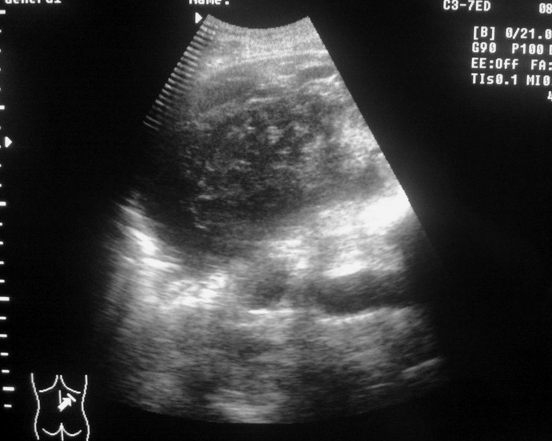

Снимки 2-3 - не в брюшной ли полости жидкость?

Жидкость в БП не обнаружена?

Что это есть такое?

Травма+анемия+ЭТО =?

Если маркеры стоят правильно, то это поддиафрагмальная внутрибрюшная гематома.

Возможно и внутрибрюшная, а может и подкапсульная гематома. Кстати, каковы критерии диф.диагноза?

Это по идее должно быть правой почкой. Между ней и печению - карман Моррисона - полость брюшины.